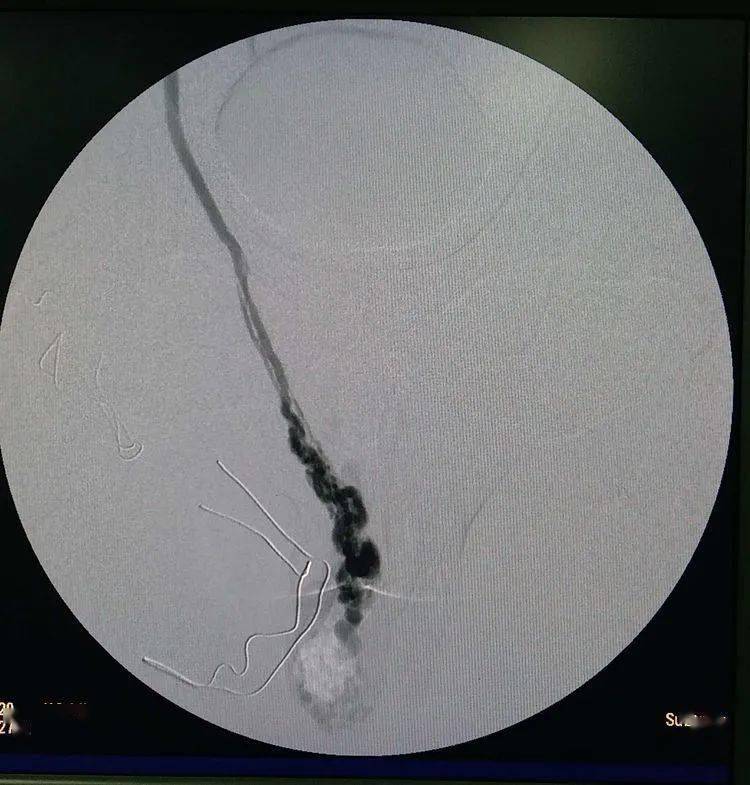

股静脉入路,选入左侧生殖静脉造影!可以发现精索静脉曲张

右侧精索静脉术后造影

右侧精索静脉曲张术前造影